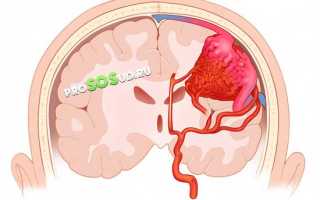

Следует отметить, что именно сосудистые аномалии становятся причиной возникновения ангиом в 95% случаев. Опухоли, расположенные на поверхности кожи, не представляют серьезной угрозы. Однако гораздо более опасны образования, затрагивающие мозг.

Поскольку заболевание связано с риском кровоизлияний, его необходимо быстро диагностировать и лечить. В противном случае могут возникнуть серьезные последствия, такие как инсульты, нарушения мозговой деятельности и эпилептические припадки.

Специфические каверномы наполняются кровью и иногда достигают значительных размеров. Осложнения возникают из-за хрупкости стенок сосудов, что может привести к мозговому кровоизлиянию.

Каверны, представляющие собой сосудистые полости, являются основой этой серьезной патологии. Кавернозная ангиома головного мозга — это крайне опасное заболевание. Стенки каверномы разделены тонкими и не очень прочными перегородками. В случае разрыва образования может произойти мозговое кровоизлияние, что в свою очередь может привести к летальному исходу.

Медики называют кавернозную ангиому бомбой с замедленным действием. Кровоизлияние может произойти в любой момент, и предсказать этот критический момент крайне сложно. Запущенная форма заболевания может привести к серьезным нарушениям сознания, а также к параличу значительных участков тела.